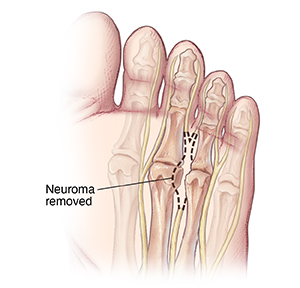

Neuroma removal

The enlarged part of the inflamed nerve is removed. Most often, you can bear weight on your foot right away. You may have to wear a surgical shoe for a few weeks. When healed, a small area may feel numb, where part of the nerve was taken out.